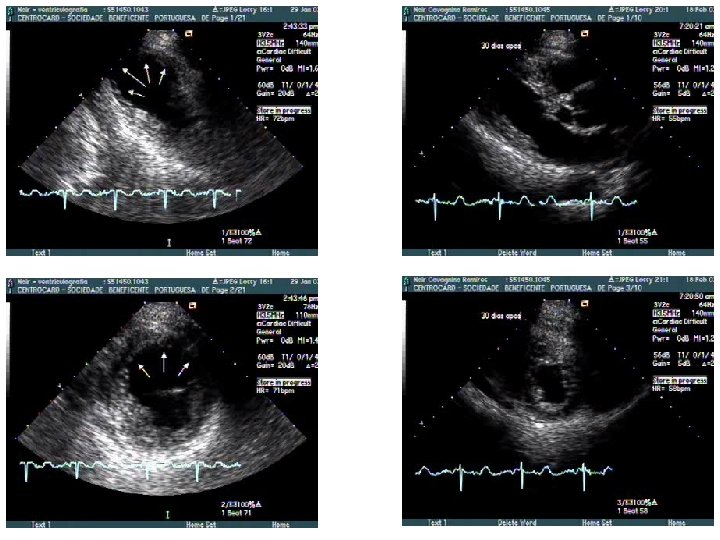

Repouso 4 c diástole Dipiridamol 4 c 2 c diástole 4 c sístole 2 c sístole

r e p o u s o 4 c diastole 2 c diastole 4 c sístole 2 c sístole D I P t o t al antes cirurgia 30 dias cirurgia 4 c diastole 2 c sístole